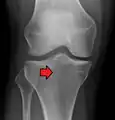

Lipohemarthrosis (presence of fat and blood from bone marrow in the joint space after an intraarticular fracture) seen on X-ray in a person with a subtle tibial plateau fracture

Lipohemarthrosis due to a tibial plateau fracture

Subtle tibial plateau fracture on an AP X ray of the knee

Lipohemarthrosis due to a tibial plateau fracture- A tibial plateau fracture seen on X-ray